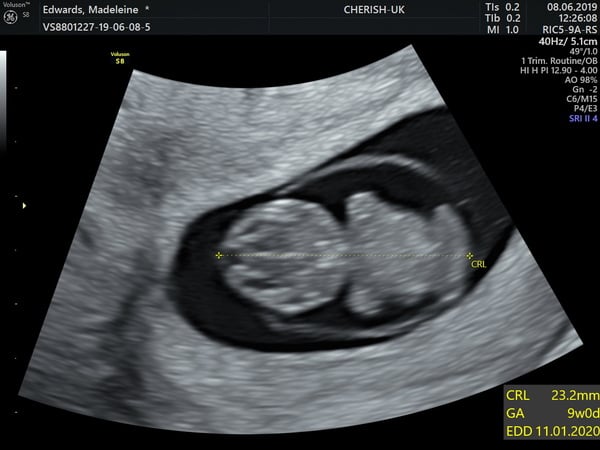

Hi all, I don't post on here too much as I find it hard to keep up! But just dropping in to say, we had an early scan today because of the miscarriage earlier this year. Baby doing absolutely fine; strong heartbeat, brain development, did a little wriggle and even measuring a day ahead so am apparently 9 weeks bang on 😃

Lovely photo @Fivebyfive2 congratulations

@fivebyfive2 that is a beautiful scan photo so clear. Congratulations x